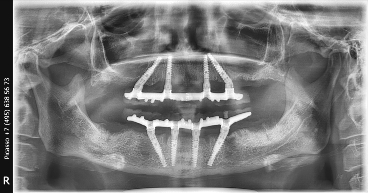

All-on-4 на рентгеновских снимках

От оценки полной или частичной адентии (полного или частичного отсутствия зубов) проводится анализ и плотности костной ткани. Основная резобция (убыль) костной ткани происходит в дистальных отделах.

Верхняя и нижняя челюсть имеют разные навигационные ориентиры для установки дистальных имплантатов (установленных под углом) и глубины погружения. На верхней челюсти ограничением является ориентир, где отчетливо видно кривую петлю синуса гайморовой пазухи (мембрана Шнейдера). Для того, чтобы пазуха осталась целостной, не перфорированной, мы не выходим за этот ориентир при работе с костью и инсталляции имплантата.

На верхней челюсти для достижения ТОРКа (стабильности имплантата, относительно костной ткани,) необходима бикортикальная установка имплантата.

ТОРК – это величина стабильности имплантата при конечном погружении в кость (в гребень), определяется динамометрическим ключом, должна быть не менее 35-40 H/Cм2.

С нижней челюстью процесс более прагматичный в связи с тем, что конгломерат костной ткани не имеет пазух и является целостным. Установка происходит внутри двусторонних ментальных отверстий (окончаний нижнего альвеолярного нерва). Определение вертикальной и горизонтальной резорбции на нижней челюсти корректирует длину и диаметр установленных имплантатов. Костная ткань на нижней челюсти имеет среднюю плотность и выше.

Далее рассмотрим параметры введения протеза и что же все-таки такое балка и зачем она нужна. Самое важное условие при винтовой фиксации протеза к мультиюнит-аббатментам это его пассивное введение. Шахта титанового рукава в протезе должна четко и точно быть конгруэнтна шахте мультиюнит-абатмента. Введение болтика при винтовой фиксации и прикручивание протеза, не должно иметь внутреннего напряжения - дотяжка на 15 Н/см2 не должна иметь никаких боковых смещений. Также важно понимать, что на этом этапе, для успешного результата протез не дотягивается плотно к кости альвеолярного гребня, активно не дожимается, чтобы не было выталкивающего движения и негативного воздействия на незажившие имплантаты. Протез на первом этапе прилегает только к слизистой и функционирует на расстоянии зубной нити, между базой протеза и костными структурами гребня.

Сразу после операции делаем протез на балке, который входит в стоимость операции, для того чтобы нагрузка в 4 кг на каждый имплантат складывалась 4+4+4+4 а балка равномерно распределяла на все имплантаты для максимального исключения перегрузки (бруксизм) во время сна. Балка распределяет нагрузку на большую площадь. Работают все имплантаты установленные по протоколу All-on-4; самое важное исключить локальную нагрузку на один имплантат.